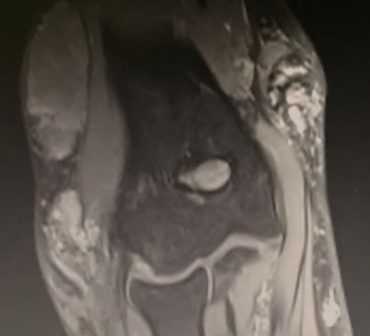

МРТ локтевого сустава в сагиттальной плоскости. Отмечается повышенное скопление свободной синовиальной жидкости в полости локтевого сустава. Синовиальная оболочка умеренно гипертрофирована.